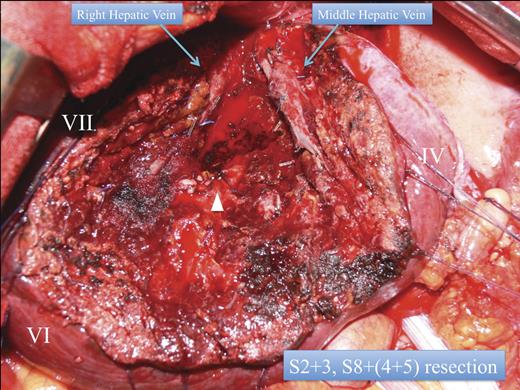

In order to obtain efficient bile duct tumour clearance as well as to maintain liver function (15-min retention rate of Indocyanine green: 19%), the patient underwent anatomic S8 resection and lateral segmentectomy (Fig. 3). The metastasis in the lateral segment demonstrated intra bile duct tumour growth.

Anatomic lateral segmentectomy, and S8 segmentectomy. White arrow head: the right pedicle.

Although there was B3 intra bile duct growth, there was no pathological evidence of malignancy in the left main bile duct. For the S8 metastases, systemic S8 resection with indigo carmine S5 counter strain had also been performed. Subsequently, normal anatomic lateral segmentectomy was performed without extra hepatic bile duct resection or cholecystectomy. His clinical course was stable without complications, and he was discharged after 7-days of hospitalisation. The patient is currently suffering from amyotrophic lateral sclerosis, without any sign of local metastatic tumour recurrence 14 months post-operatively.